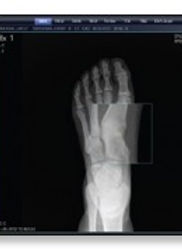

Our state-of-the-art imaging provides clear, detailed images quickly and safely, helping us diagnose and treat foot conditions effectively.